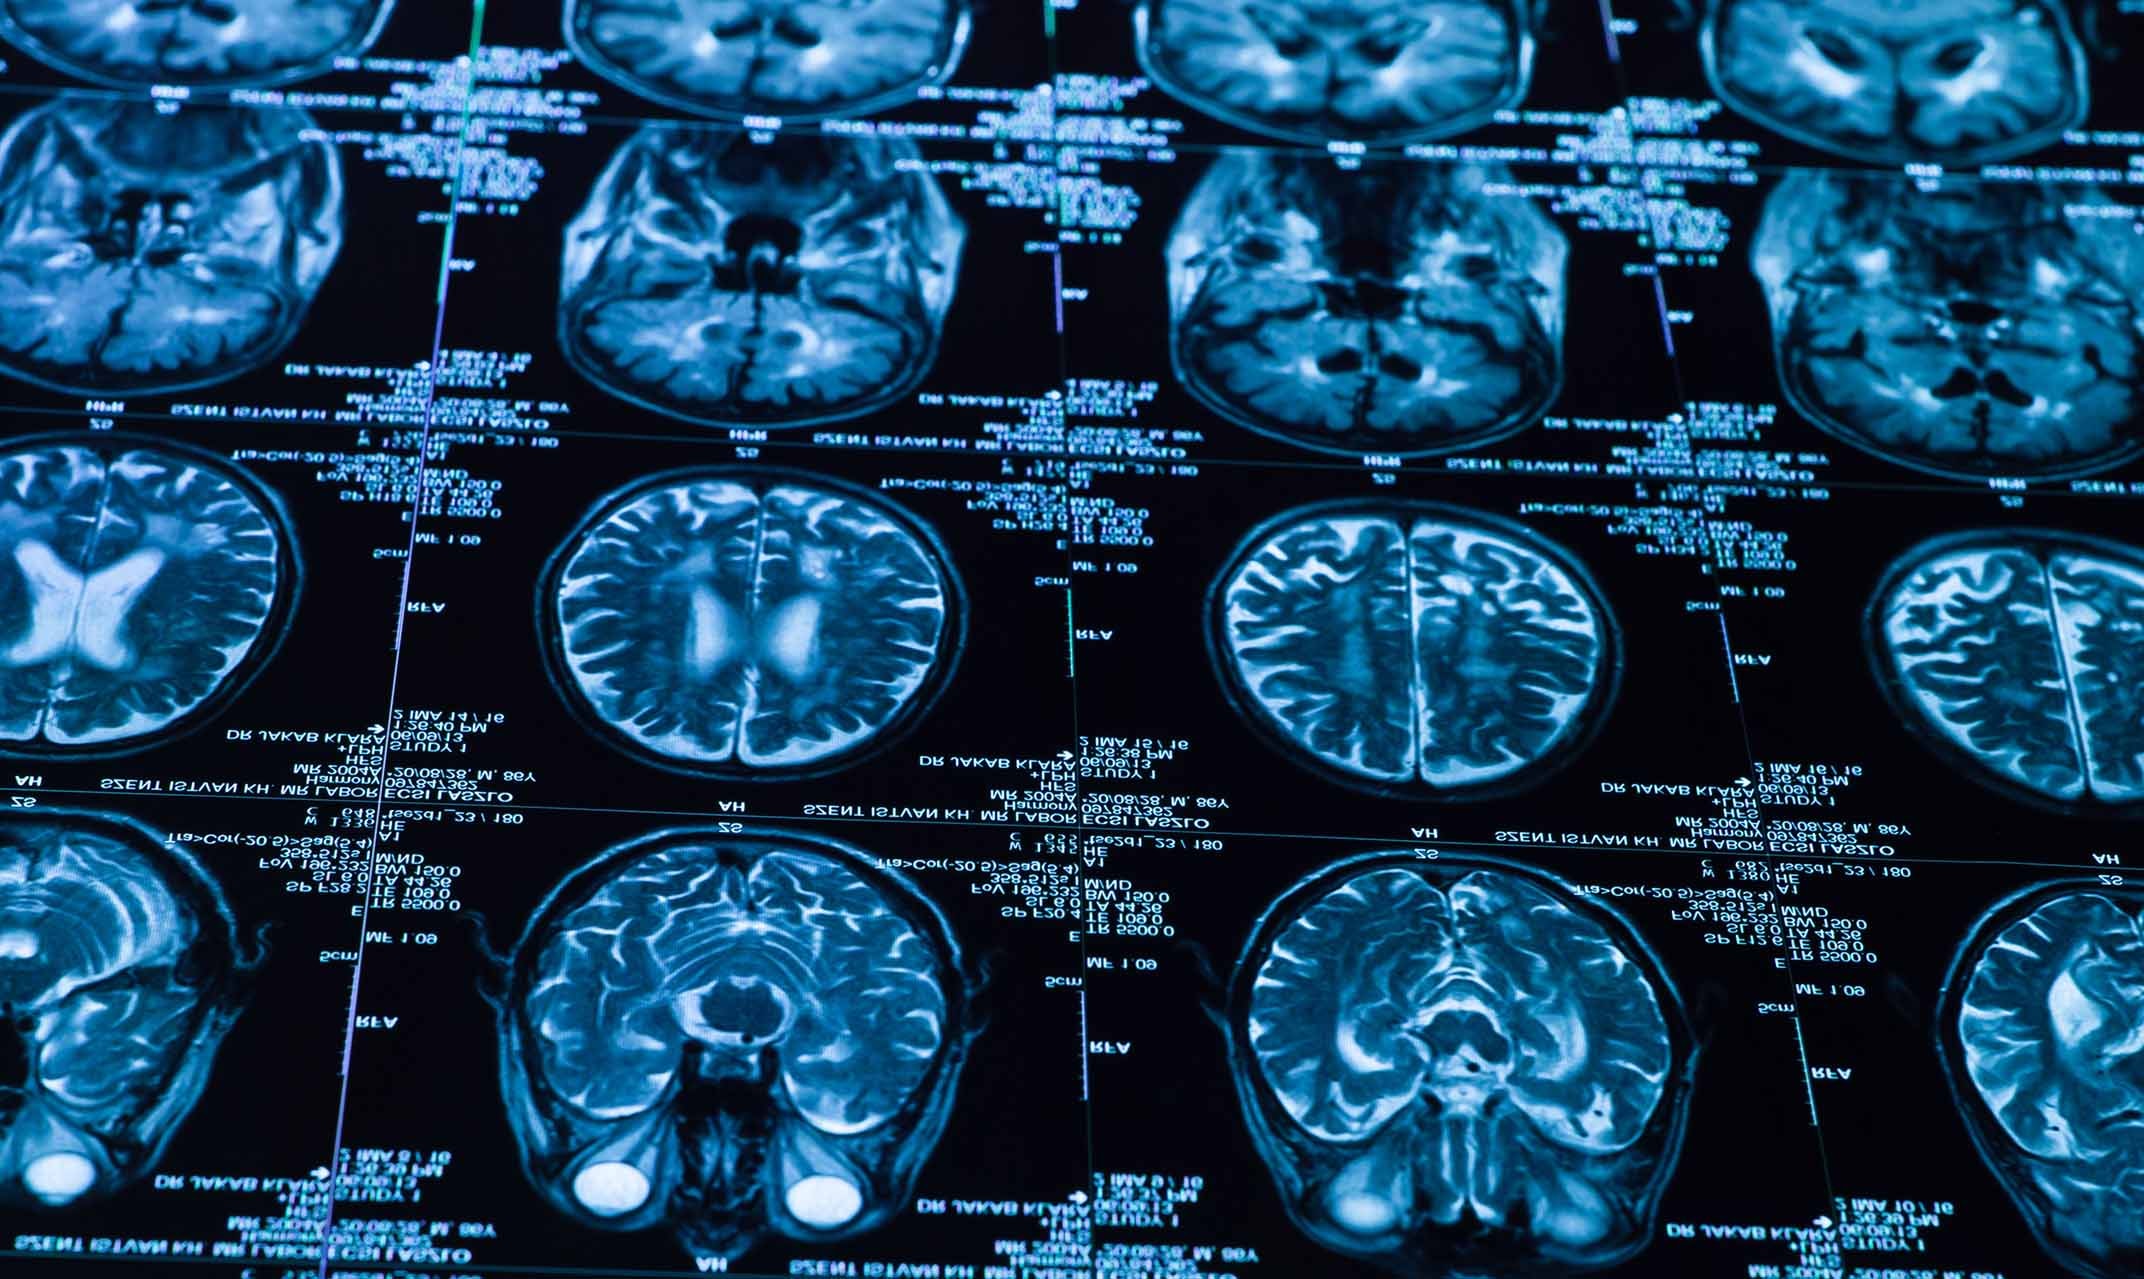

Ser víctima de una lesión en la cabeza puede causar desde mareos, vómitos, estado de coma, discapacidad e incluso la muerte, según los Centros para el Control y la Prevención de Enfermedades (CDC, por sus siglas en inglés). Las lesiones cerebrales traumáticas (LCT), también conocidas como traumatismos craneoencefálicos (TCE), son tan comunes como potencialmente peligrosas. Es una lesión que ocurre cuando una fuerza externa impacta el cerebro, provocando daños de diferentes grados de severidad.

La causa de una LCT puede variar entre una simple caída hasta accidentes de tráfico, golpes directos en la cabeza o impactos violentos. Y pueden ser devastadores para las personas que lo sufren. En algunos casos, el daño es inmediato, lo que resalta la urgencia y gravedad de ciertas lesiones cerebrales traumáticas. Pero, ¿cuáles son los efectos a largo plazo de las lesiones cerebrales traumáticas? A continuación, te brindamos más información.

Cuando una persona sufre un golpe fuerte en la cabeza, puede experimentar desde síntomas leves hasta consecuencias graves y permanentes. La lesión cerebral puede afectar funciones cognitivas, motoras y emocionales, dependiendo de la gravedad y el área afectada.